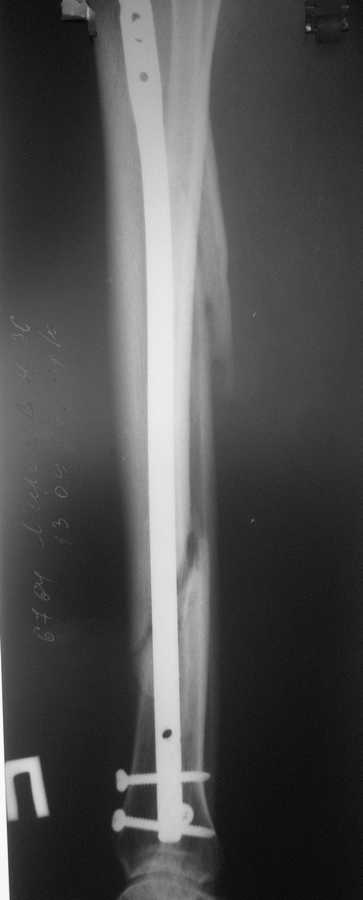

В январе 2009 года нами оперирована пациентка с переломом н\3 голени штифтом Expert. Динамизация через 4 месяца, пациентка при этом уже ходила с тростью. Дома периодически передвигалась без дополнительной опоры.

В настоящее время - через 9 месяцев с момента операции периодически в вечернее время беспокоят ноющие боли в места перелома (не постоянно). При беседе выяснено, что боли чаще беспокоят после того, как днем она походит по дому без трости. Пальпаторно по гребню берцовой кости болей нет, но по задне-внутренней поверхности б\б кости пальпирутеся западение на уровне места перелома.

Имя     : через 9 месяцев (2).jpg

Тип     : image/jpeg

Размер  : 20983 байтов

Описание: отсутствует

Url     : http://weborto.net:8080/pipermail/ortho/attachments/20090913/ceda924c/attachment-0004.jpg